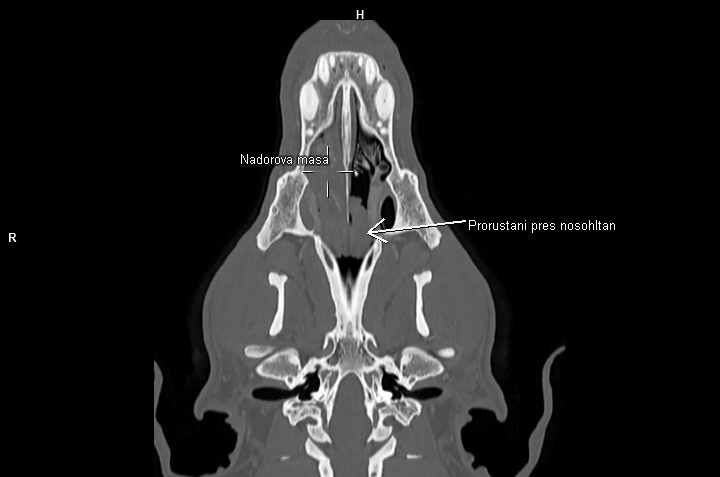

Nedílnou součástí diagnostiky ve veterinární onkologii se tak stává CT vyšetření. Velká spirální CT spolu s použitím kontrastní látky nám umožňují velmi detailní zobrazení i hlubokých struktur těla, stav okolních měkkých tkání, průběh velkých cév v bezprostředním okolí a přítomnost metastáz. Lze pak mnohem přesněji cíleně odebrat bioptické či cytologické vzorky z patologické tkáně, určit operabilnost nádoru a v případě nálezu metastatického rozsevu zvážit další postup (chemoterapie, ozařování atp.)

• nádory dutin nosních.